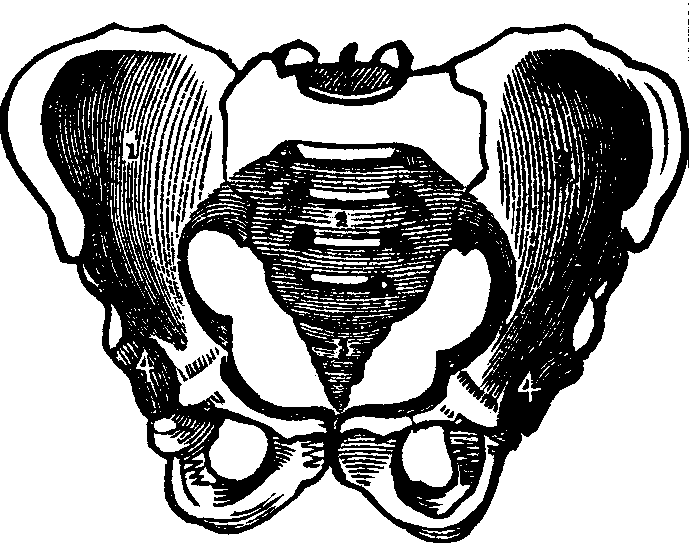

Fig. 15. A representation of the pelvic bones. e. The

lumbo-sacral joint. 2. The sacrum. 3. Coccyx. 1, 1. The

innominata. 4,4. Acetabula.

The Pelvis is an open bony structure, consisting of the Os Innominata, one on either side, and the Sacrum and Coccyx behind. The Sacrum, during childhood, consists of five bones, which in later years unite to form one bone. It is light and spongy in texture, and the upper surface articulates with the lowest vertebra, while it is united at its inferior margin to the coccyx. The Coccyx is the terminal bone of the spinal column. In infancy it is cartilaginous and composed of several pieces, but in the adult these unite and form one bone. The Innominata, or nameless bones, during youth, consist of three separate pieces on each side; but as age advances they coalesce and form one bone. A deep socket, called the acetabulum, is found near their junction, which serves for the reception of the head of the thigh-bone.